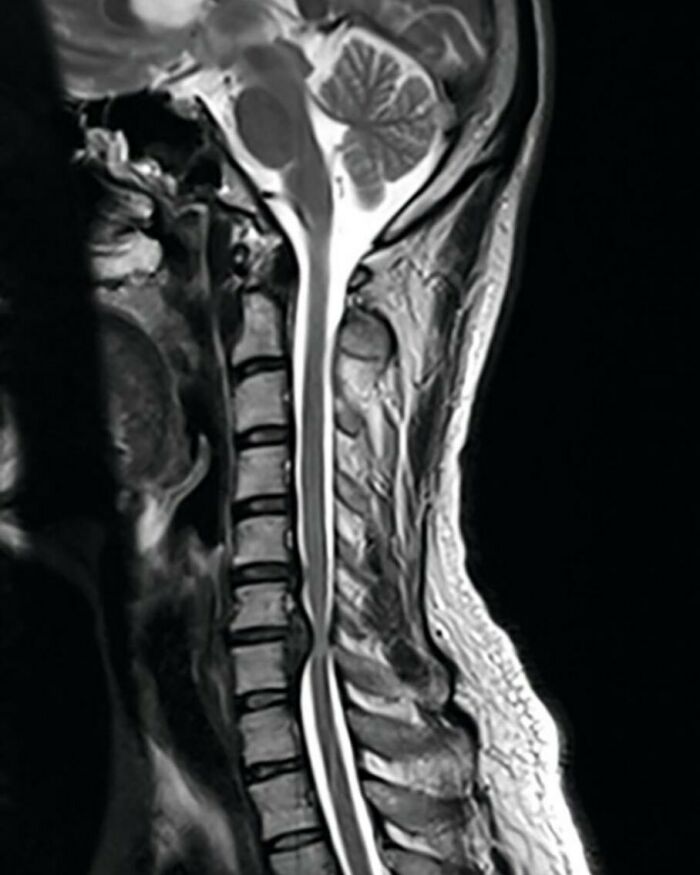

MRI of spinal cord (sagittal view) showing vertebral disc herniation and spinal cord compression at the level of C6-C7